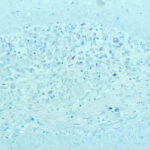

The histopathologic picture in nontuberculosis mycobacterioses is just as variable as the clinical picture and may present nonspecific acute and chronic inflammation, suppuration and abscess formation, or tuberculoid granulomas with or without caseation . In some instances, both tissue reactions occur concurrently. The presence or absence of acid-fast bacilli depends on the tissue reaction. In suppurative lesions, numerous acidfast bacilli often can be found. |

Infection with Mycobacterium Kansasii M. kansasii is usually a lymph node and pulmonary infection, and skin lesions are unusual. Implantation causes a chronic cutaneous nodule and sometimes ulceration . The lesions are often crusted. There may be sporotrichoid lymphatic spread of lesions up the extremity . In immunocompromised patients, such as those with HIV infection, there may be multiple visceral lesions (lung and bone) with hematogenous dissemination to skin. The skin lesions are acute abscesses with large numbers of acid-fast bacilli . |

Acid-fast bacilli usually can be identified in histologic sections of early lesions that show a nonspecific inflammatory infiltrate. In contrast, tuberculoid granulomas generally no longer show acid-fast organisms unless areas of central necrosis are present. Although primary lesions usually require a few months for the formation of tuberculoid granulomas, the sporotrichoid nodules that arise later show tuberculoid granulomas and a lack of acidfast bacilli even when they have been present for only a few weeks. |

Histopathology. The infection begins as a subcutaneous nodule exhibiting "ghost" ischemic-type dermal collagen and fat necrosis with deposition of fibrin and hematoxyphilic extracellular clumps of mycobacteria. Ulceration proceeds as the epidermis loses its vascular supply. Ziehl-Neelsen stains reveal vast numbers of acid-fast bacilli in the necrotic fat ; their distribution is often irregular. A variable degree of neutrophil infiltration and thrombosis of vessels are also observed. In time, a nonspecific granulation tissue or a granulomatous reaction commences from the depth and sides of the ulcer; healing and re-epithelialization take place with considerable scarring. Acid-fast bacilli decline rapidly in number during healing . The histopathologic case definition for Buruli ulcer, useful for research studies, is (a) the typical pattern of infarctivelike necrosis of deep dermal collagen and fat and (ideally, but not always found in limited samples) (b) nearby clusters of acid-fast bacilli. |

PCR technology has been used to track the distribution of M. ulcerans in Buruli ulcer lesions and to compare the mycobacterial burden with histopathologic changes . While peaks of mycobacterial DNA and histopathologically recognized acid-fast bacilli in the necrotic base of the ulcers marked the position of the primary infection focus, mycobacterial DNA (and sometime microcolonies) was also present in samples from the periphery of the ulcers and occasionally from macroscopically and histologically healthy-looking excised tissue margins and in sites where satellite lesions were developing. Even when granulomas provided evidence for the development of cell-mediated immunity, development of satellite lesions by contiguous spreading was not completely prevented. |

Healing of Buruli ulcer coincides with development of delayed hypersensitivity to the mycobacterium, possibly contingent on the cessation of mycolactone production. In a recent study, expression of cytokines was correlated with the inflammatory response evaluated by histopathology . All of the cases showed extensive necrosis and chronic inflammation. The most important feature correlating with chronicity was considered to be the presence or absence of granulomas coexisting with a mixed proinflammatory/antiinflammatory cytokine balance. Granulomas were absent from relatively early ulcerative lesions, which contained more bacilli and little interferon (IFN}-gamma, suggesting that at this stage of the disease strong suppression of the protective cellular immune response facilitates proliferation of bacilli. When granulomas were present, significantly higher expression of IFN-gamma was seen as well as lower bacillary counts. |